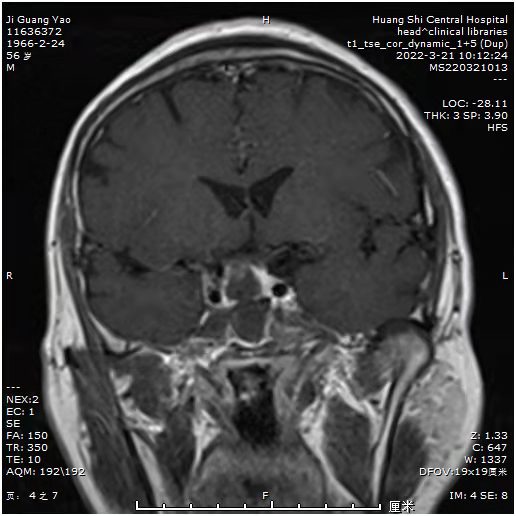

患者近期视力明显下降,一侧视力只有0.1,而且感觉眼部肿胀不适。MRI:发现鞍区占位。常规CTA,发现鞍区小动脉瘤!如果先处理动脉瘤,介入需支架辅助,术后需口服抗凝药物,近期3个月内,不能手术。患者必将失明!怎么办?和患者及科室血管介入组沟通后,患者意愿强烈,先行垂体瘤手术,做好术中动脉瘤破裂可能,带上动脉瘤夹,备用。

可见动脉瘤和垂体瘤很近